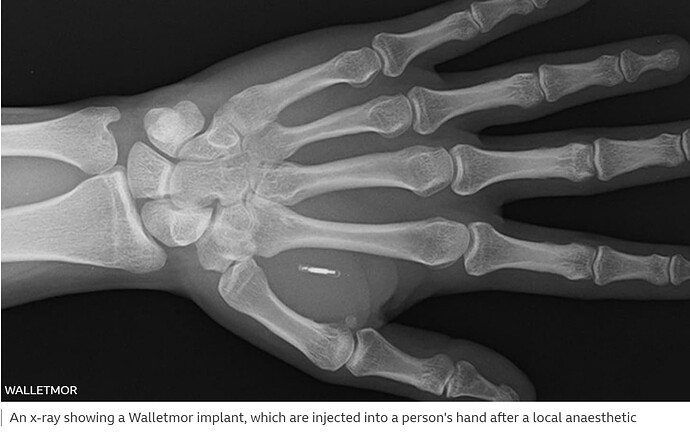

Walletmor’s chip, which weights less than a gram, is comprised of a tiny microchip and an antenna encased in a biopolymer - a naturally sourced material, similar to plastic.